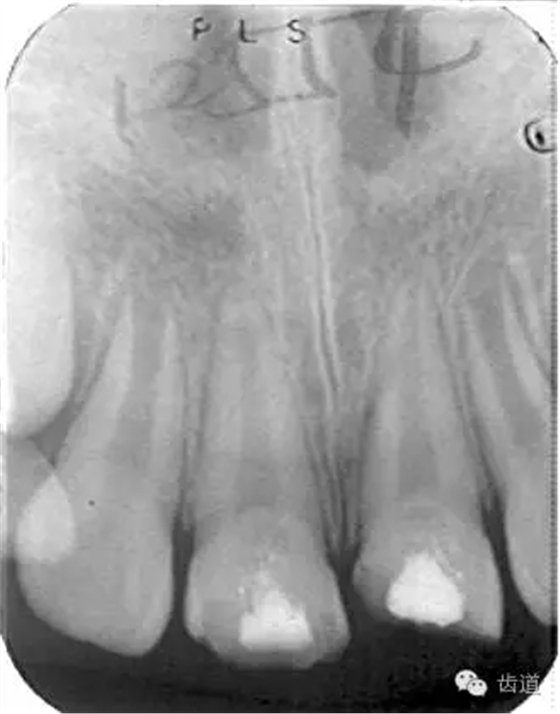

術(shù)后三個(gè)月

術(shù)后六個(gè)月

術(shù)后兩年